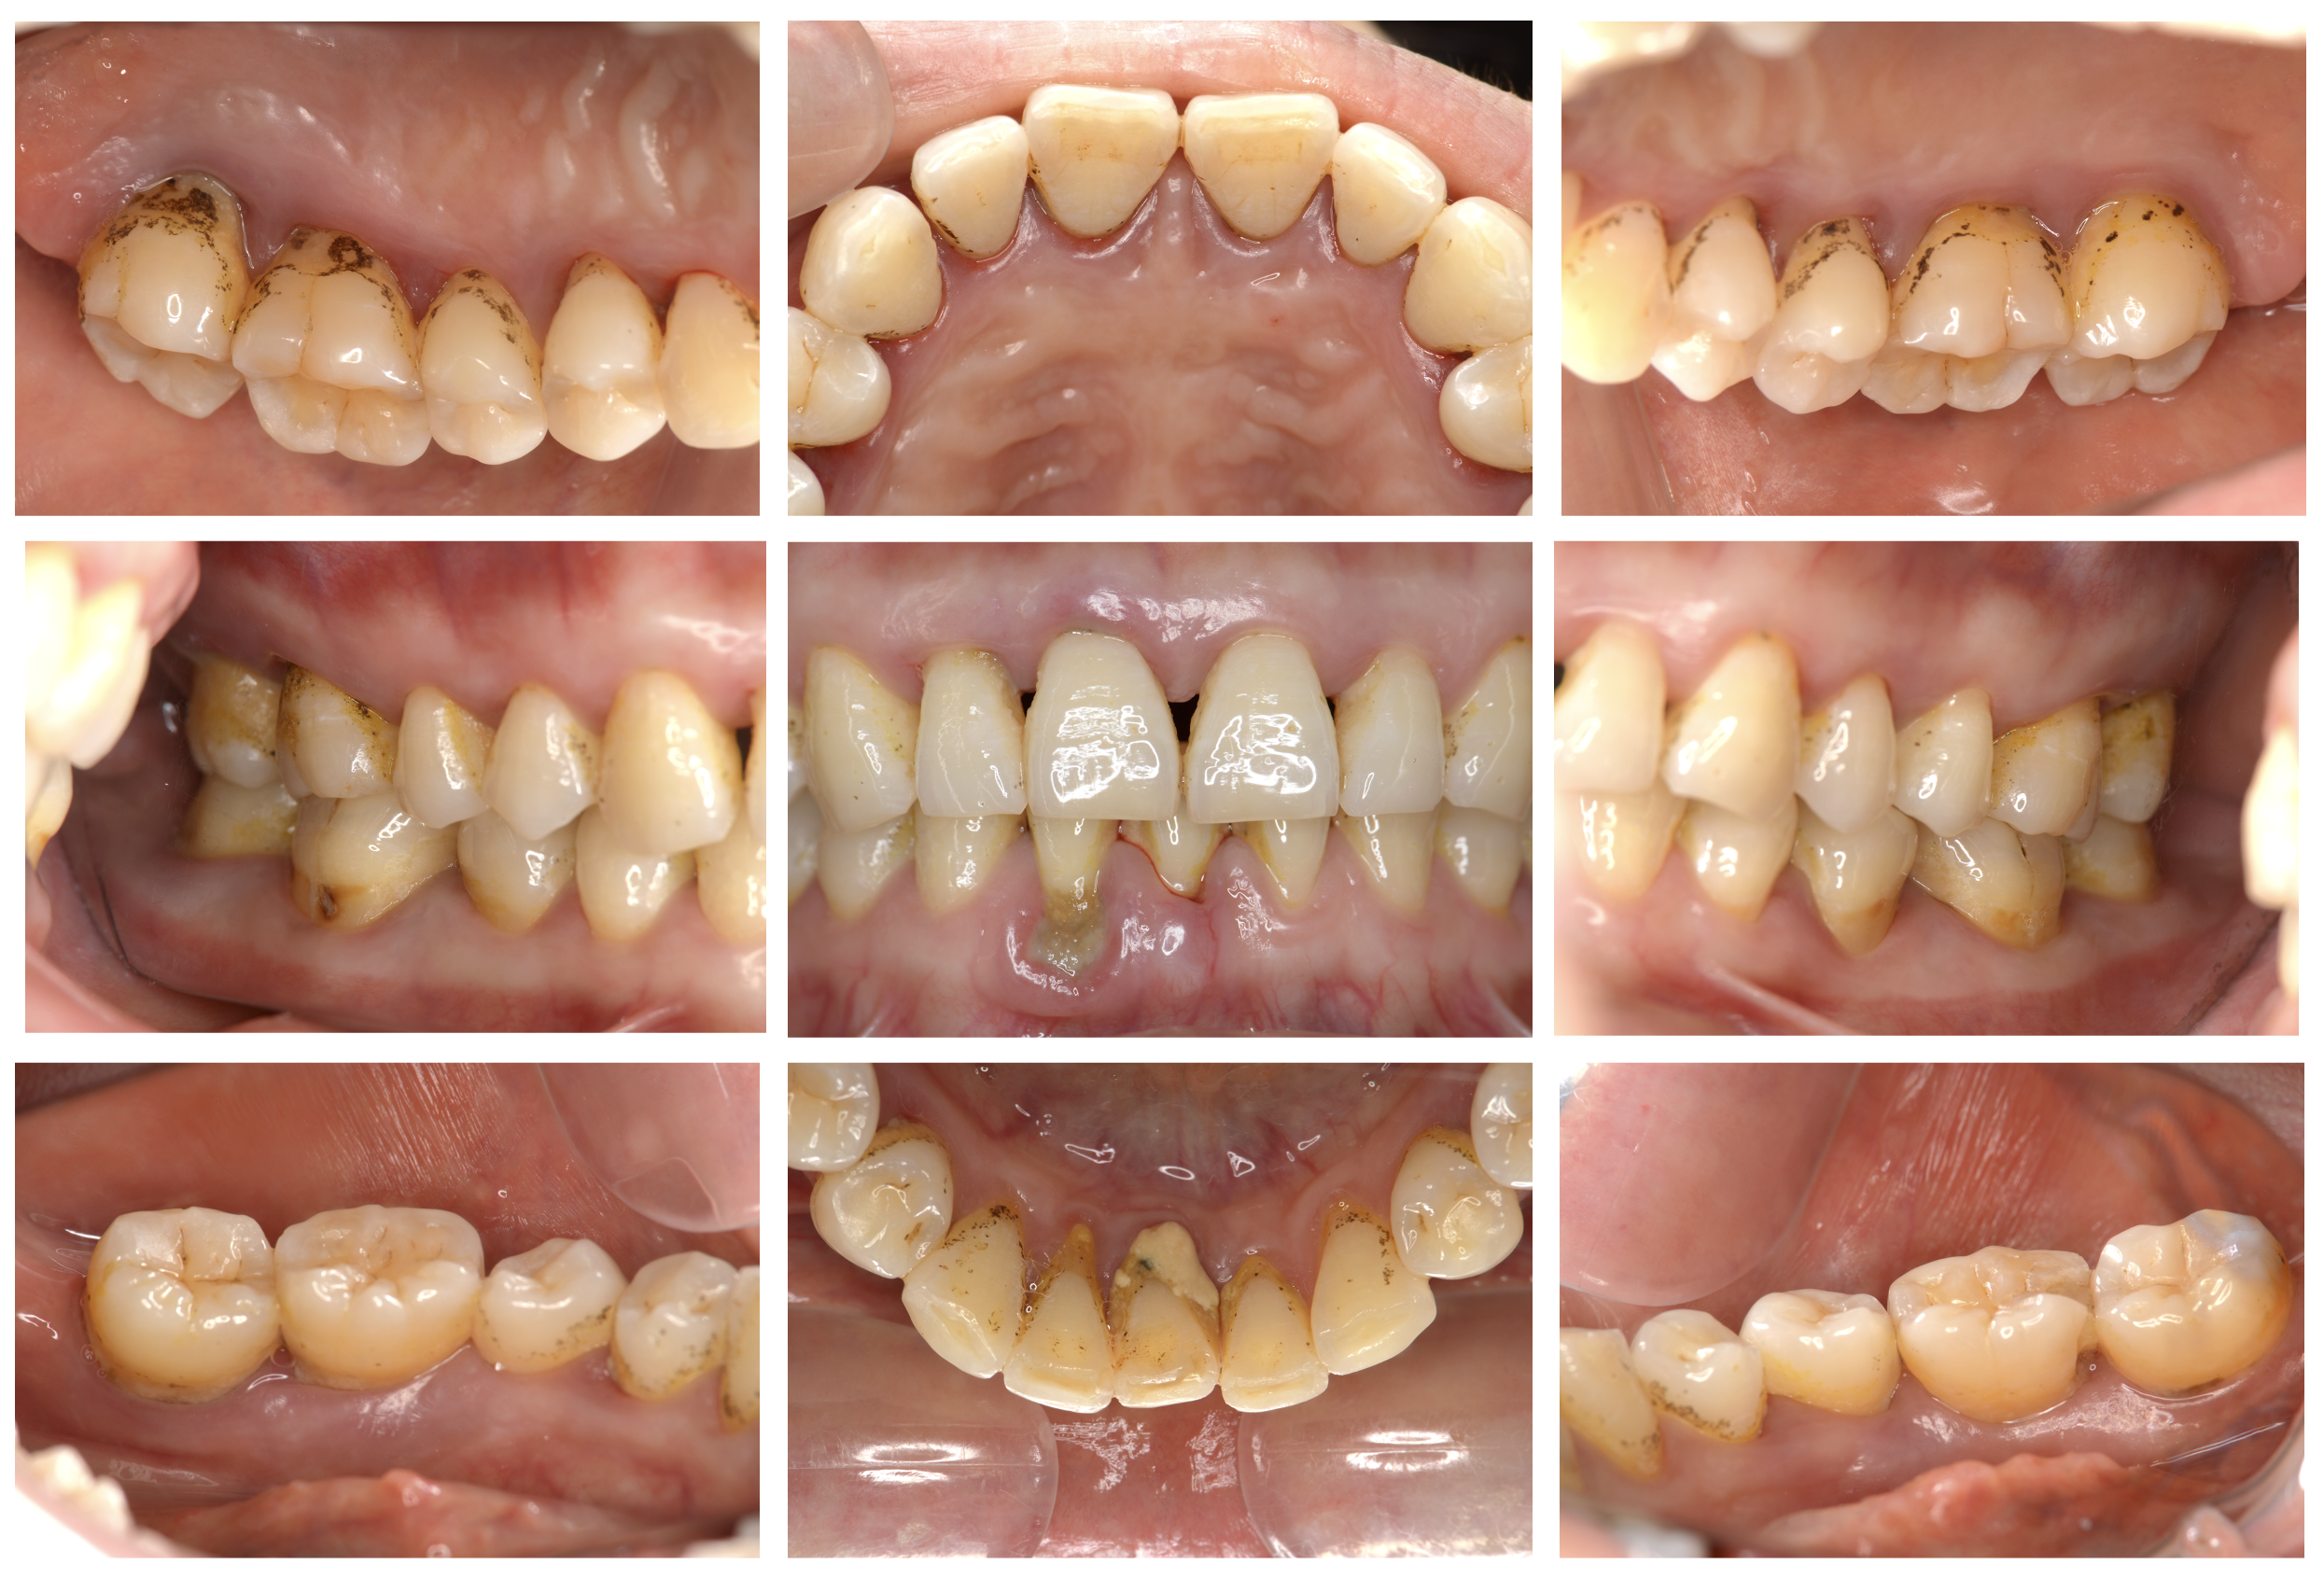

歯茎が腫れて痛い。歯ブラシの時にすごく出血する。

初診時

歯周基本治療後

| 主訴 | 歯茎が腫れて痛い。歯ブラシをする際に出血する。 また、家族から口臭を指摘されたのでしっかり治したい。 |

|---|---|

| 治療内容 | 精密検査を行った結果、歯周ポケット(歯と歯茎の間の溝)の深さが4 mm以上の部位が全体の72%以上で、最大10 mmであった。またエックス線画像からは歯槽骨(歯を支える骨)の著しい(歯の根の1/3~2/3程度)吸収を確認した。重度慢性歯周炎(ステージⅢ グレードC)と診断し、歯周治療を開始した。 歯周基本治療として徹底したブラッシング指導と歯肉縁上スケーリング並びに6ブロックに分けた歯肉縁下歯石の除去を行った。再評価検査の結果、病状安定と判断できる歯周組織の状態となったためため歯周外科治療は行なわずにメインテナンスへ移行した。 |

| 治療期間 | 2ヶ月半(週に1回) ブラッシング指導 歯肉縁上スケーリング スケーリング・ルートプレーニング |

| 費用 | 保険治療 |

| リスク・副作用 | 著しい歯槽骨の吸収を認めていたため、歯周治療により歯茎が引き締まった結果、歯肉退縮(歯茎がざること)が生じた。これにより、知覚過敏や根面う蝕(むし歯)のリスクが高まった。 ブラッシングが不十分になってしまうと再発の可能性があるため3ヶ月に1度のメインテナンスを行なっている。 *当院では歯周治療により生じる可能性のあるリスク等について治療前に説明しております。 |